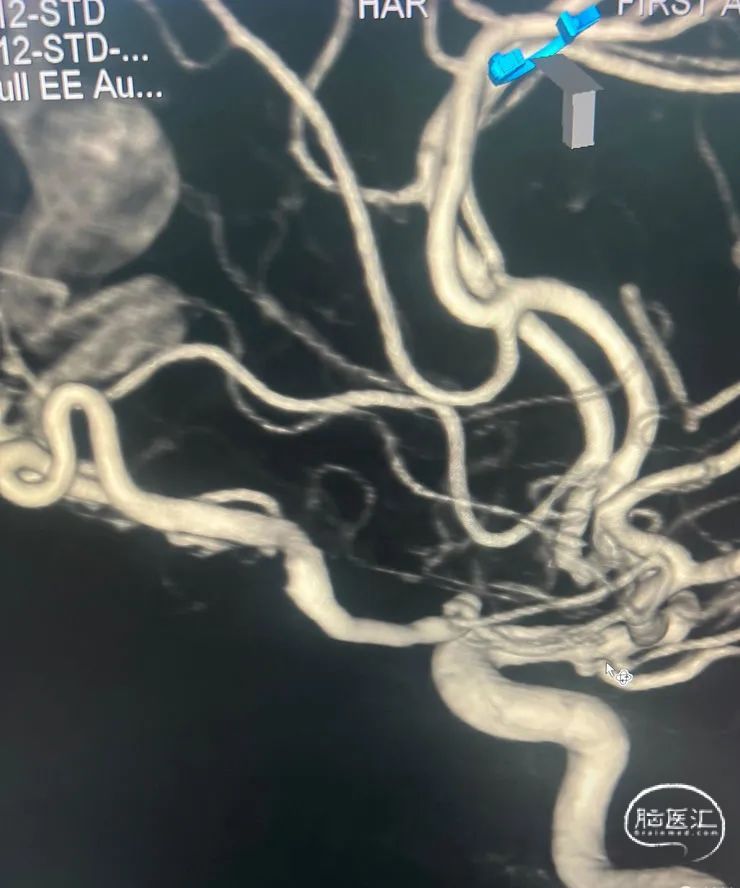

治疗经过

手术过程

第一根微导管到位。

第二根微导管到位及填圈所形成的塞子。

R-ica。

R-颈外也参与供血。

L-ica。

L-颈外也参与供血。

病人穿刺双侧股动脉鞘,通过左侧颈内动脉——眼动脉途径栓塞,右侧颈内动脉造影检查瘘口栓塞后情况。我们可以看到瘘口被栓得越来越少。